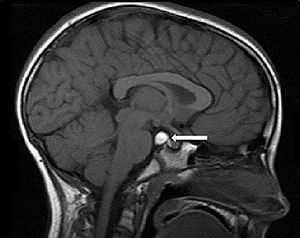

Следующим звеном в диагностике герминомы головного мозга является применение КТ и МРТ головного мозга. Томографические методы исследования позволяют установить опухолевый характер образования, его размеры и расположение. Примерно у 40% больных с герминомой головного мозга выявляется характерный для этой опухоли признак — опухолевая инфильтрация зрительных бугров и наличие расположенного в середине петрификата (симптом бабочки). В пользу герминомы могут говорить распространение опухолевого процесса по боковым желудочкам и метастазирование в инфундибулярную область III желудочка.

Следующим этапом обследования является проведение КТ (компьютерной томографии) и МРТ (магниторезонансной томографии) головного мозга. На этой стадии устанавливаются размеры, расположение и характер новообразования.